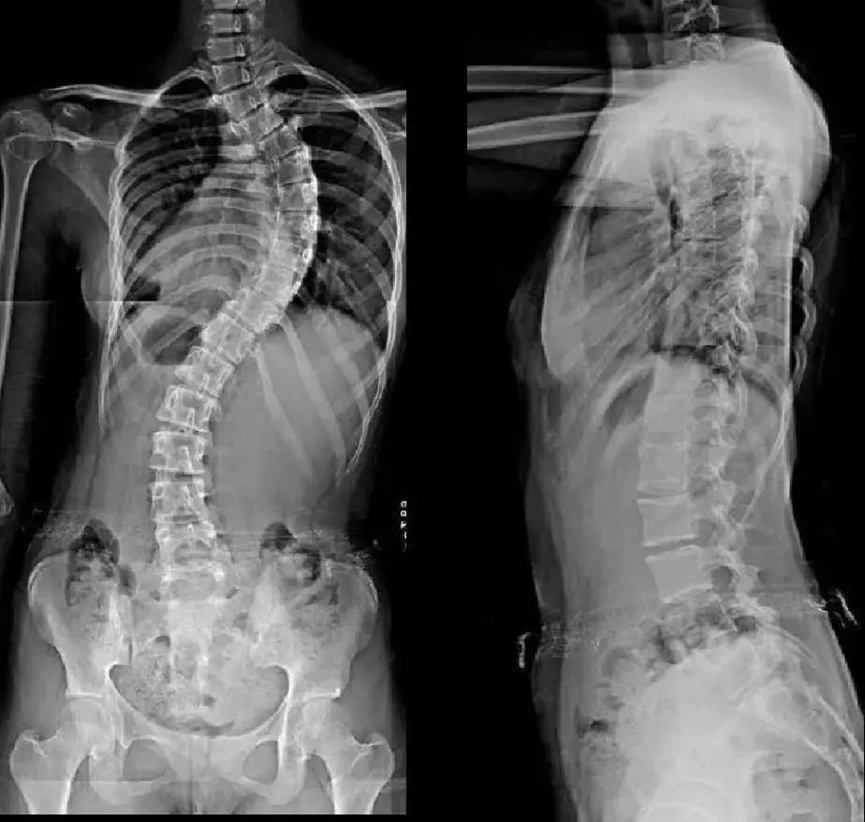

正常人的脊柱从后面看应该是一条直线,并且躯干两侧对称。如果从正面看有双肩不等高或后面看到有后背左右不平,就应怀疑“脊柱侧凸”。这个时候应拍摄站立位的全脊柱X线片,如果正位X线片显示脊柱有大于10度的侧方弯曲,即可诊断为脊柱侧凸。轻度的脊柱侧凸通常没有明显的不适,外观上也看不到明显的躯体畸形。较重的脊柱侧凸则会影响婴幼儿及青少年的生长发育,使身体变形,严重者可以影响心肺功能、甚至累及脊髓,造成瘫痪。轻度的脊柱侧凸可以观察,严重者需要手术治疗。

当初步怀疑有脊柱侧弯时, X线脊柱全长检查是明确诊断的重要检查,此项检查可以明确脊柱具体侧弯角度。进一步出现脊髓压迫症状,怀疑椎体、椎间盘病变时,则需要加做脊柱全长CT或脊柱全长MRI,明确病变情况。